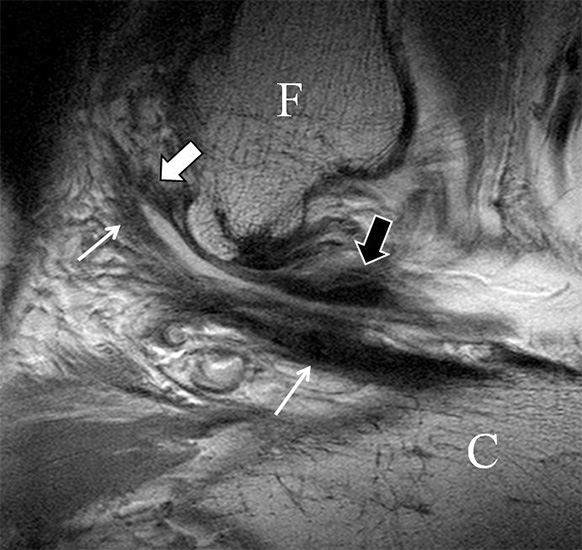

b. T2 fs axial. Infraktion des hinteren Volkmann‘schen Dreiecks (schmale, weiße Pfeile). Hier inserierende, intakte, hintere Syndesmose (breite, weiße Pfeile).

Das Ligamentum tibiofibulare posterius (hintere Syndesmose) verläuft flacher und geht nach kranial in das Ligamentum tibiofibulare interosseus und nach kaudal in das Ligamentum intermalleolare posterius über. Letzteres bildet ein artikuläres Labrum zwischen Trochlea und Talus 9.

Da also die hintere Syndesmose an der posterioren Tibia inseriert, entspricht eine Fraktur oder Infraktion des hinteren Volkmann`schen Dreiecks funktionell einem knöchernen Ausriss des Ligamentum tibiofibulare posterius (Abb. 18 a und b). Aufgrund der Koinzidenz von Syndesmosenläsionen mit Innenbandverletzungen ist bei der Beurteilung gesondert auf solche zu achten.